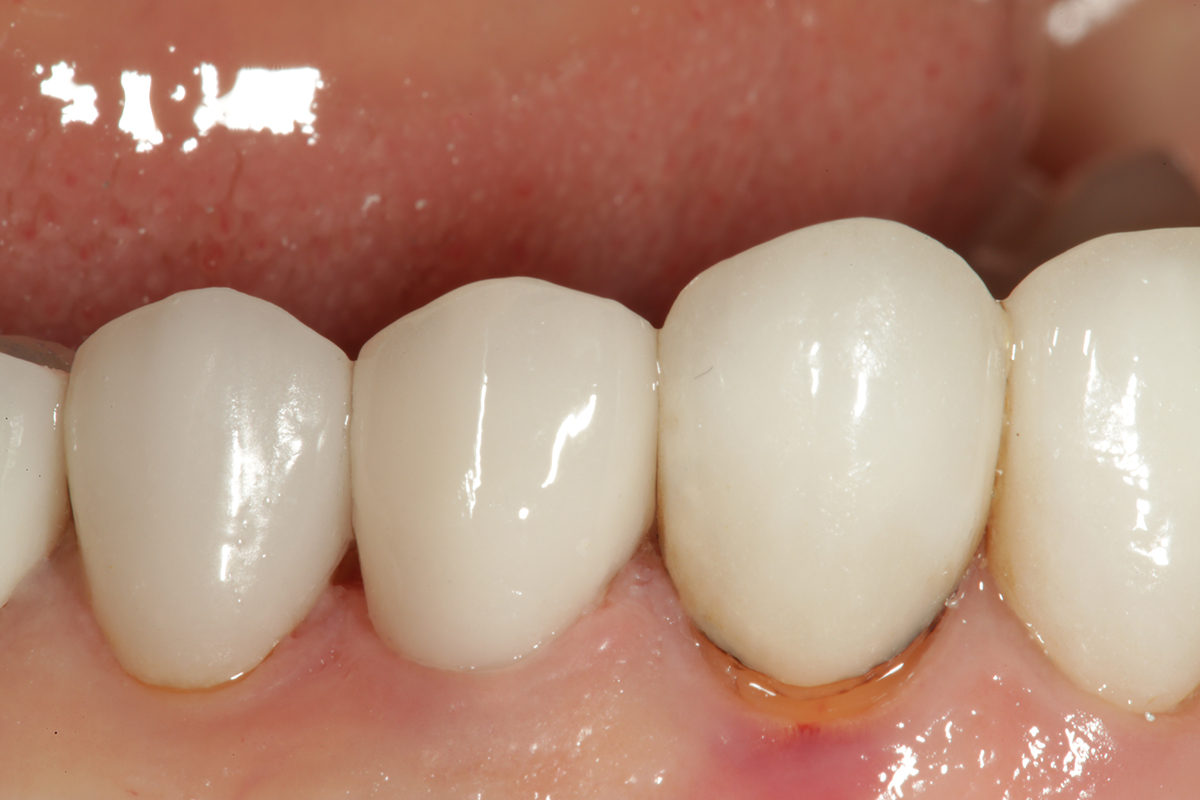

Fig 20. A facial view of the completed cementation.

Figure 20